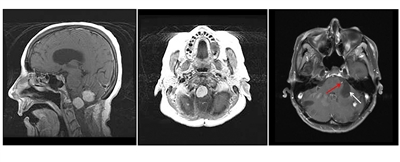

Los hemangioblastomas son la manifestación más común en los pacientes con enfermedad de VHL y afectan a más del 70 % de las personas. En un estudio prospectivo se evaluó la evolución natural del los hemangioblastomas.[16] La media de edad de aparición de los hemangioblastomas del sistema nervioso central (SNC) es de 29,1 años (intervalo, 7–73 años).[17] Los hemangioblastomas del SNC se observaron con mayor frecuencia en el cerebelo (45 %), la médula espinal (36 %), la cola de caballo (11 %) y el tronco encefálico (7 %).[18] Aunque los hemangioblastomas esporádicos son casi siempre solitarios por naturaleza, las lesiones en el SNC asociadas a la enfermedad de VHL a menudo son multifocales. Luego de una media de seguimiento de 7 años, el 72 % de 225 pacientes estudiados presentaron lesiones nuevas.[18] En las figuras 2 y 3 se muestran hemangioblastomas de cerebelo y médula espinal, respectivamente, en pacientes con enfermedad de VHL.